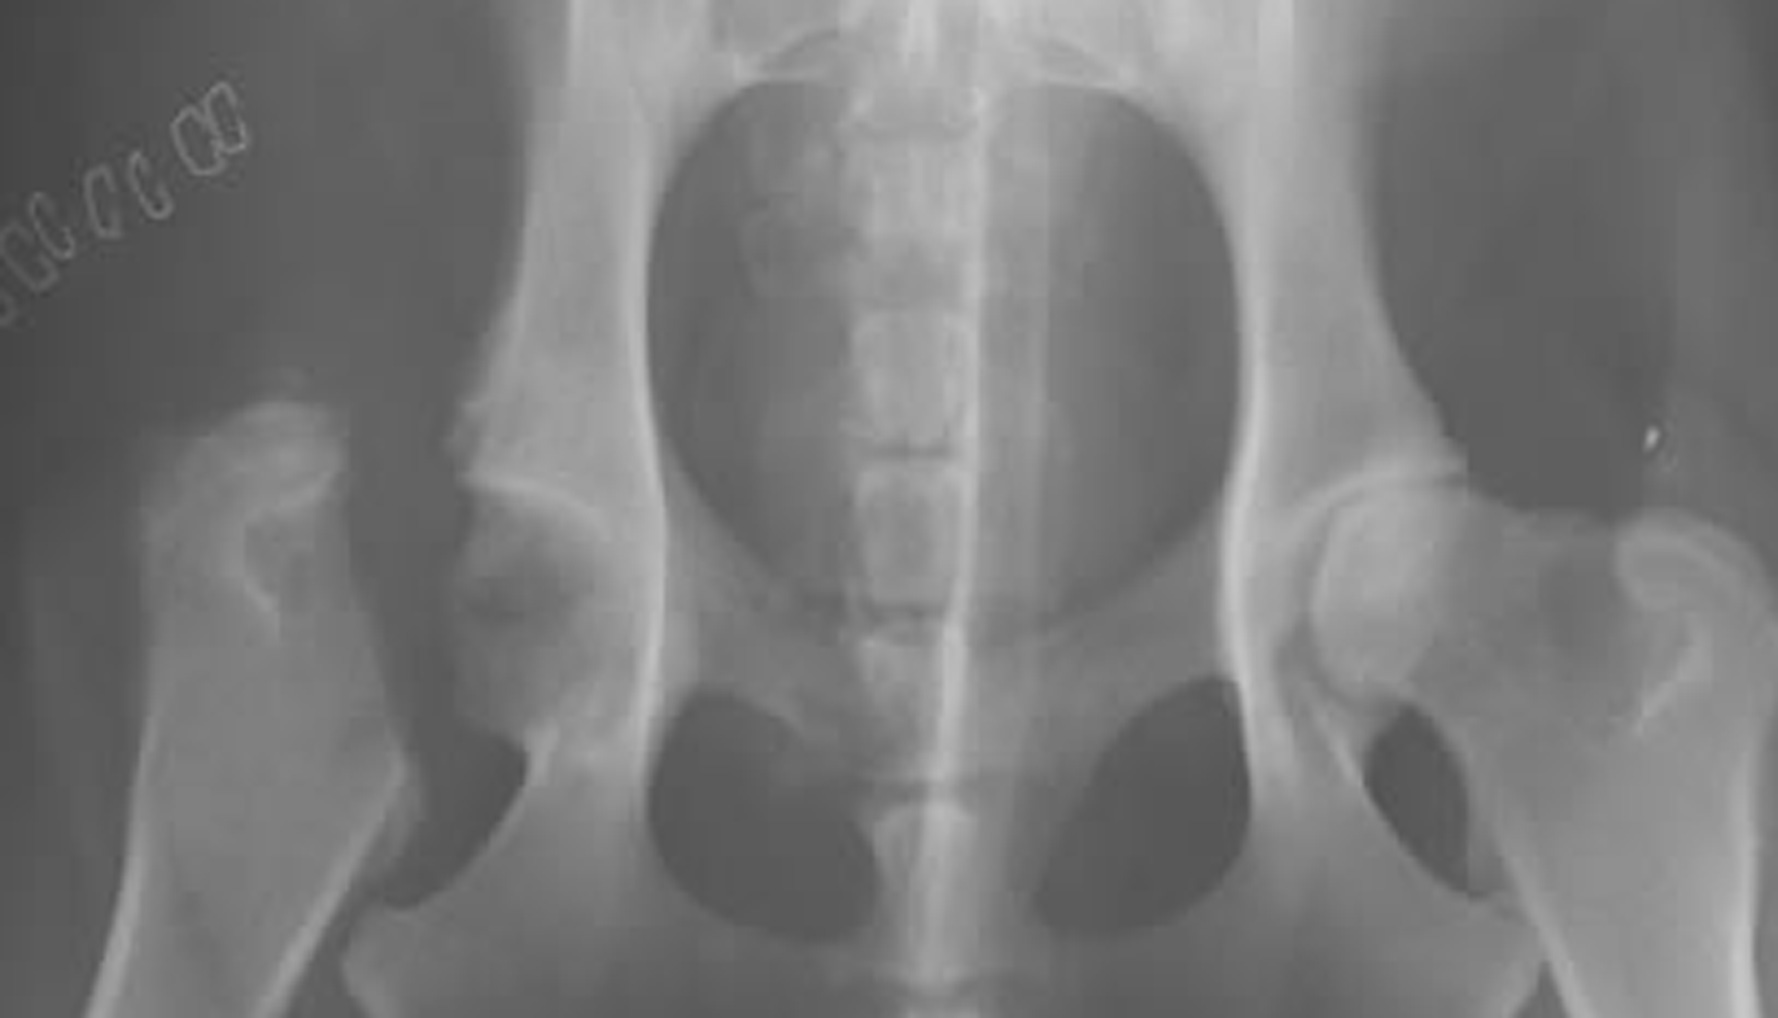

FHO surgery

During the FHO surgery, the surgeon will remove the femoral head leaving the socket portion of the hip empty. Your dog's leg muscles will initially hold the femur in place as scar tissue develops between the femur and acetabulum.